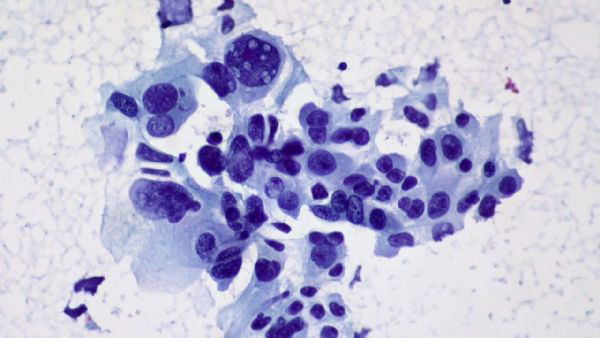

理論上講,進入到腫瘤裡面的殺傷性T細胞應該是為了殺滅癌細胞而生的。但是,Newell的團隊卻發現,患者腫瘤組織里面不僅有殺滅癌細胞殺傷性T細胞;還有大量與癌症無關的、原本應該是識別病毒的“旁觀者”殺傷性T細胞,這些T細胞根本就“不認識”癌細胞。

跟癌症相關的殺傷性T細胞被癌細胞幹趴下了,周圍是一群沒有抗癌能力的旁觀者殺傷性T細胞

尤其是在那些預後差的癌症患者腫瘤組織中,旁觀者殺傷性T細胞佔比更多。這些旁觀者殺傷性T細胞眼看著有殺癌細胞能力的T細胞被腫瘤組織耗竭,不會伸以援手,所以免疫檢查點抑制劑拿這幫T細胞也是沒辦法了。